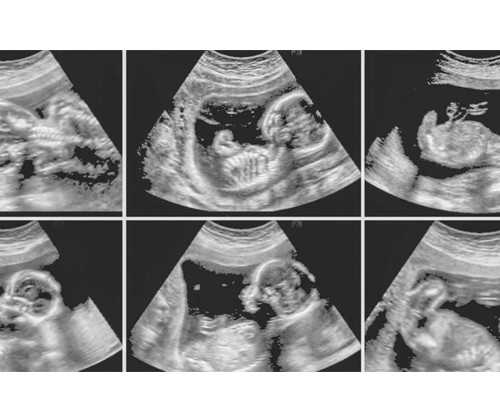

PGD技术主要助孕括以下几个步骤:母细胞和公细胞结合形成受精卵,受精卵培养至囊胚阶段,然后进行细胞活检,提取细胞进行基因检测。在这个过程中,只有发育到囊胚阶段的胚胎才能被取样进行基因检测。

虽然三代试管婴儿是通过PGD技术获得的,但并不是所有的受精卵都会发育成囊胚。根据统计数据显示,在经过PGD技术助孕后,大约50%-70%的受精卵可以发育为囊胚。